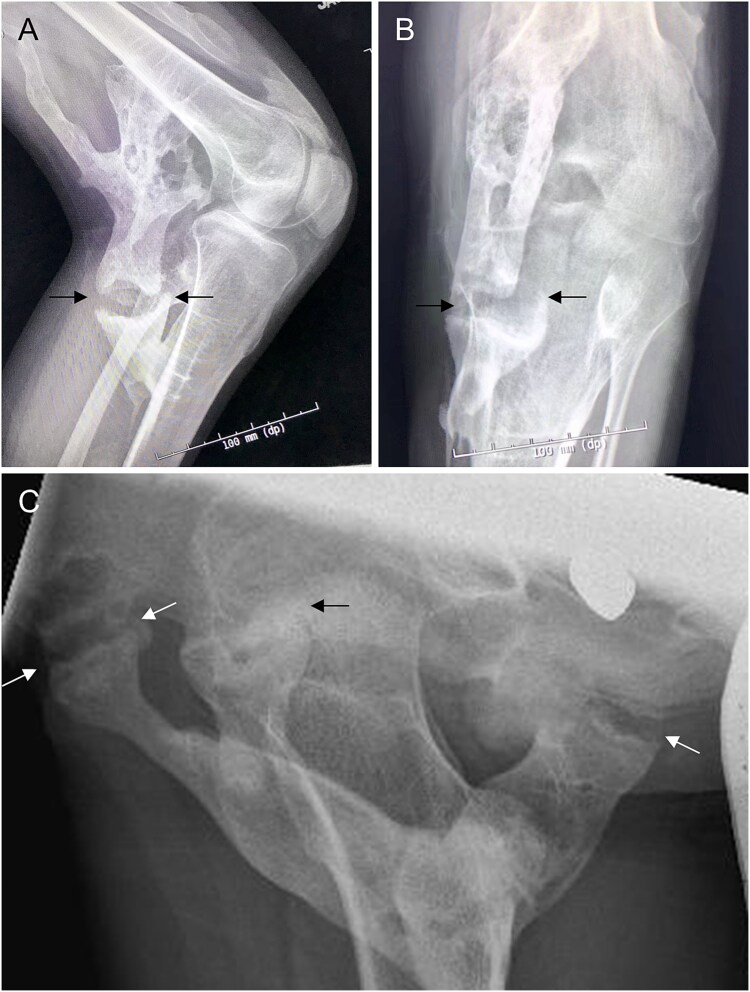

假关节(假关节)是正常异位骨骼骨折愈合的并发症,但在异位部位未见报道。进行性骨化纤维发育不良(FOP)是一种极其罕见的遗传性疾病,其特征是进行性异位骨化(HO)和先天性骨骼异常,包括正常位置骨骼的发育性关节病。在这里,我们报告了6例FOP患者的异位假关节形成,所有这些患者都发生在疼痛发作和膝关节、髋关节和前臂软结缔组织的HO之后。据我们所知,FOP是唯一发生异位假关节形成的人类疾病。这些发现支持来自突变ACVR1的BMP通路信号失调不仅介导HO,还介导异位假关节的形成,并且异位假关节可以由新生的肌肉骨骼元件引起。

Pseudoarthroses (false joints) occur as a complication of fracture healing in the normotopic skeleton but have not been reported at ectopic sites. Fibrodysplasia ossificans progressiva (FOP) is an ultra-rare genetic disorder characterized by progressive heterotopic ossification (HO) and congenital skeletal abnormalities including developmental arthropathy in the normotopic skeleton. Here, we report ectopic pseudojoint formation in 6 patients with FOP, all occurring after painful flare-ups and HO in soft connective tissues of the knee, hip, and forearm. To our knowledge, FOP is the only human condition in which ectopic pseudojoint formation occurs. These findings support that dysregulated BMP pathway signaling from mutant ACVR1 mediates not only HO, but also ectopic pseudojoint formation, and that ectopic pseudojoints can arise from de novo musculoskeletal elements.